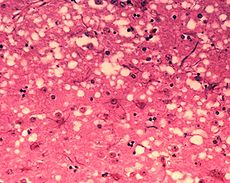

Prions — A prion is nothing more than a badly folded protein. Unlike bacteria and viruses, it has no DNA or RNA. However, it does reproduce, vampire-fashion, by converting well-folded proteins to misfolded ones, which go on to convert others. Prion structures even “grow” by forming fibrils that extend at each end. Prions are in the cause of nasty-sounding illnesses including mad cow disease, chronic wasting disease and scrapie.